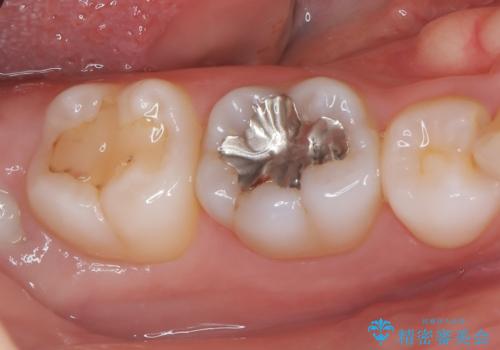

- 銀歯を外したいことを主訴に来院されました。

銀歯を丁寧に取り除き、形態を整えた上で、セラミックインレーで修復しました。